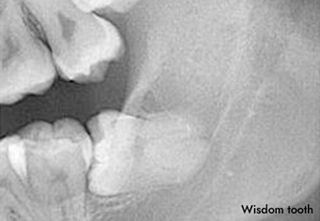

なぜ親知らずを抜かなくてはならないのか?

通常の永久歯が生える時期から大きくずれて生えるため

「親も生えたことに気づかない」ところから名付けられたとされる「親知らず」。

親知らずの生え方や生える本数には大きく個人差があり、

ときに、抜歯をしなくてはお口の健康を損ねるリスクもございます。

どのような理由で親知らずは抜歯されるのか、ケースごとにご紹介いたします。